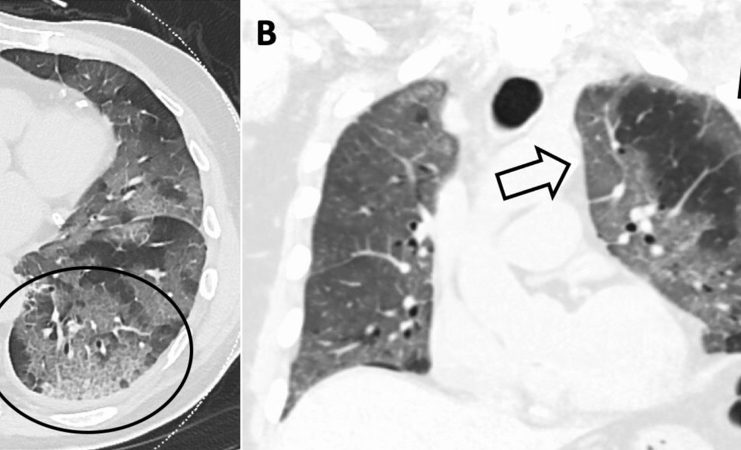

La campagna SIRM “Coronavisibile”

COVID-19: cosa il Medico Radiologo deve sapere